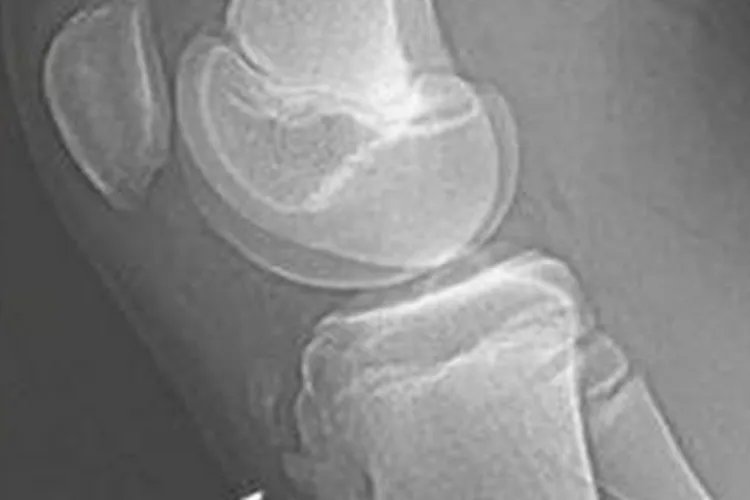

概述胫骨结节凸起是一种临床表现,存在凸起时可能会伴随疼痛、肿胀,以及活动受限表现。胫骨结节凸起的病因多是在剧烈活动过程中,髌骨韧带及胫骨结节撕脱损伤导致。症状胫骨结节凸起时会伴随出现膝部疼痛症状,并且在行走、上下楼梯、跑跳时疼痛加重,严重时甚至可出现跛行,影响日常活动。另外,触摸胫骨结节处可发现膝部还存在局限性肿胀。

病因胫骨结节是股四头肌通过髌骨和髌韧带附着的骨骺,剧烈运动时,比如踢球、快跑等,会导致股四头肌强力收缩,通过髌韧带反复牵拉胫骨结节骨骺,进而引起局部慢性损伤,出现充血、水肿或撕裂,造成局部血液循环障碍,甚至缺血性坏死,长此以往,就会导致胫骨结节骨骺肥大、隆起,即胫骨结节凸起。治疗发现胫骨结节凸起后要及时制动,减少运动量,急性期可用石膏拖将膝部保持伸直位,或进行局部封闭、按摩治疗。疼痛较重的情况也可以配合应用微波、激光、超短波等进行理疗,减轻疼痛,增加局部血液循环。若保守治疗无效,也可以遵医嘱进行手术治疗,如胫骨结节切除手术。